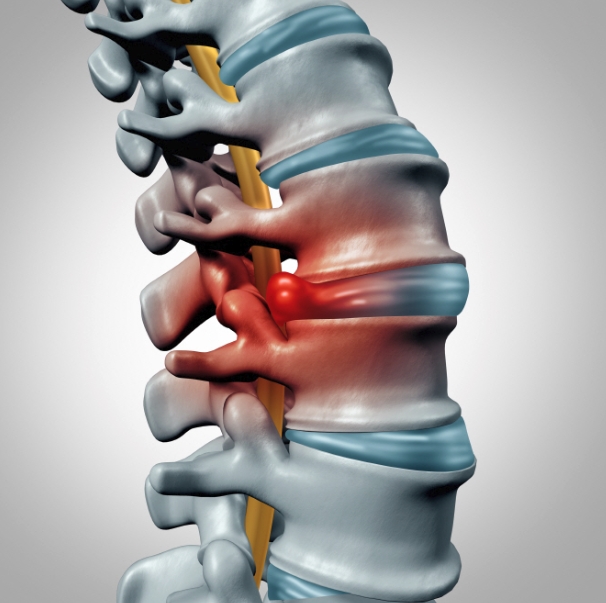

목디스크란?

목디스크는 목뼈(경추) 사이에 있는 디스크(추간판)가 손상되거나 탈출하면서 신경을 압박하는 질환입니다. 스마트폰과 컴퓨터를 많이 사용하는 현대인들에게 흔히 발생하는 문제로, 목 통증을 넘어 어깨와 팔, 손까지 영향을 줄 수 있습니다. 저도 한동안 잘못된 자세로 앉아 있는 습관 때문에 목이 뻐근하고 저린 증상을 겪었는데, 그냥 피로 때문이라 넘겼다가 더 심해진 경험이 있습니다.